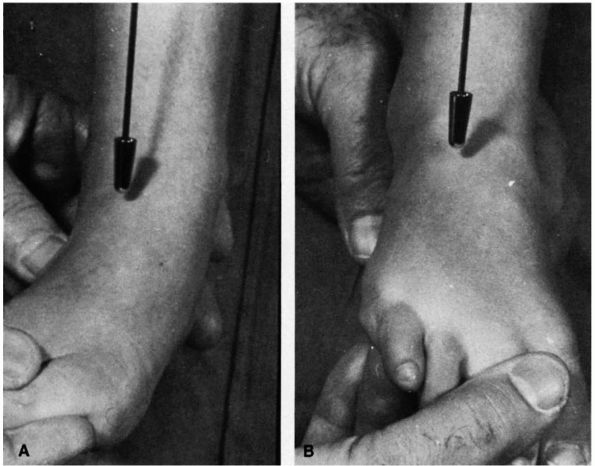

![]() |

FIGURE 20-21. Tarsal coalition. Note the position of the involved left foot with the forefoot in abduction (A) and heel in valgus (B). Also note the loss of the longitudinal arch.

generally reveals decreased hindfoot or midfoot motion, or both. Most

commonly, the heel is in valgus and the forefoot in abduction (Figure 20-21).

peroneal tendons in the lateral aspect of the ankle and foot (Figure 20-22). Attempt at inversion of the deformity causes pain and discomfort along the peroneal region (Figure 20-23).